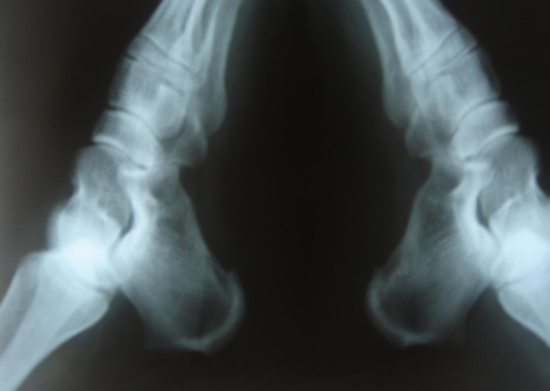

1.以跟骨骨刺为例

其原因是跟骨下前方有蹠长肌腱和蹠腱膜长时间慢性牵拉—被牵拉部位形成慢性机体,即把大量的钙质、磷质输送到这里,使这里的软组织硬化、钙化,最后骨化—新生骨在力的拉应力下最后形成前尖后阔的骨刺。刺乃尖也!故而得名。

6.跟骨刺。

7.滑囊炎。常见的有肱桡滑囊炎、坐骨结节滑囊炎、跟后滑囊炎等。